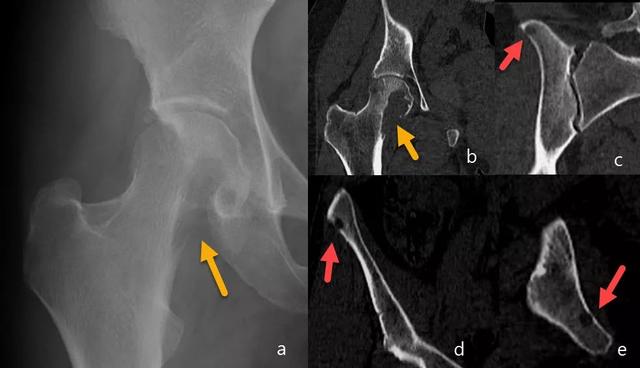

骨髓瘤的一个特征是具有“雨滴颅骨(raindrop skull)”的图案(图7和8)。

图7:骨盆X线片(a):跛行和右侧髋部疼痛的患者,右侧股骨近端明确的溶骨性病变(黄色箭头),皮质破坏。在CT研究(b,c,d和e)中,观察到多个明确边界的皮质下溶骨性病变(红色箭头),提示多发性骨髓瘤。通过骨活检确认诊断。